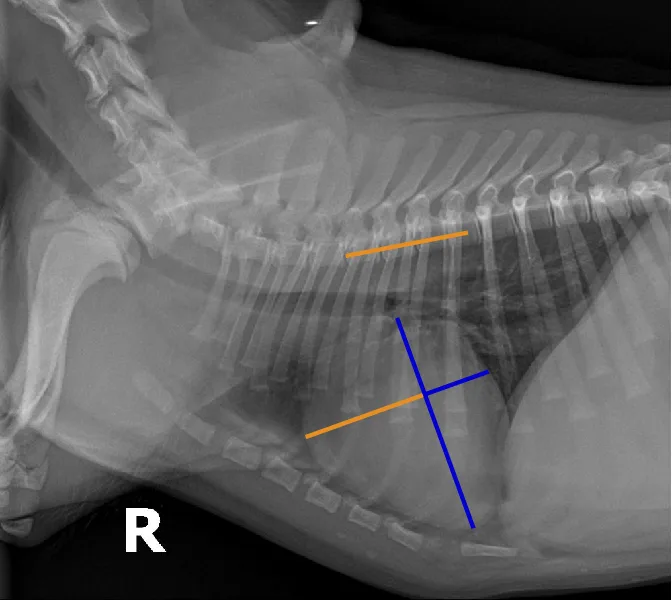

FIGURE 12 Representation of the VRHi with a value of 2.9 in a dog with a normal cardiac silhouette (left), and a dog with pulmonic stenosis and right-side heart enlargement with a VRHi value of 3.6 (right). Using the right lateral projection for measurement, a value ≥3.5 detects right-sided heart enlargement with a sensitivity of 68% and specificity of 86%.16 Images courtesy of Federico Villaplana Grosso, DACVR, DECVR, and Bruna Del Nero, DACVIM (Cardiology). Illustration courtesy of Jose Narvaez Perez